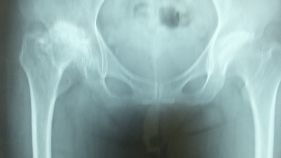

股関節のレントゲン画像

…変形性関節症の程度が確認できます

X線

• 臼蓋が形成されているかどうか・・・臼蓋形成不全の有無

• 大腿骨頭と臼蓋の間隙について・・・重なって見える場合は重症

• シェントン線などがスムーズなラインを描くかどうか・・・大腿骨頭の変形の有無、臼蓋形成不全について

• 大腿骨頭の変形・・・骨端すべり症、大腿骨頭壊死などの有無